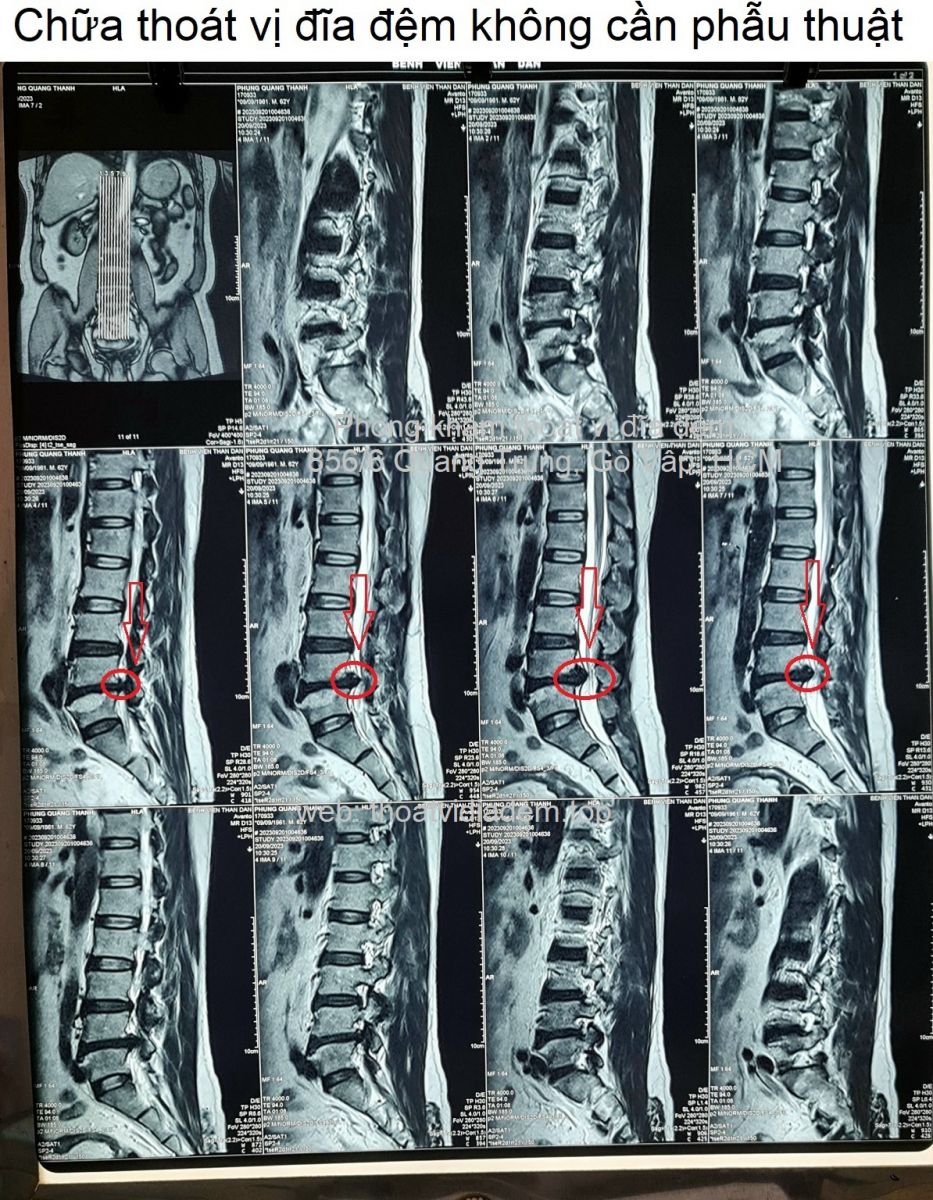

Thoát vị đĩa đệm, rách vòng xơ, chèn rễ L3 trái, chèn rễ L5 phải.Lồi kèm thoát vị đĩa đệm tầng L2-L3, di trú xuống dưới ở ngách bên trái, ép mặt trước bao màng cứng, làm hẹp ngách bên trái, chèn rễ L3 trái. Thoát vị đĩa đệm dạng trung tâm tầng L4-L5, có rách vòng xơ, có mảnh rời di trú xuống dưới ở ngách bên phải, ép mặt trước bao màng cứng, chèn ép rễ L5 phải. Thoái hóa cột sống thắt lưng.❮ đọc tiếp ❯

Thoát vị đĩa đệm dạng trung tâm, có rách vòng xơ.Thoát vị đĩa đệm dạng trung tâm tầng L4-L5, có rách vòng xơ, có mảnh rời di trú xuống dưới ở ngách bên phải, ép mặt trước bao màng cứng, chèn rễ L5 phải. Thoái hóa cột sống thắt lưng.❮ đọc tiếp ❯